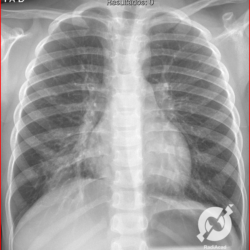

E o nome dado a esta alteração radiográfica que corresponde à substituição do ar alveolar por líquido é a consolidação alveolar.

Uma consolidação alveolar é, por definição, uma opacidade (imagem densa, branquinha) homogênea ou às vezes heterogênea (pela presença de calcificações ou cavidades), de limites mal definidos, exceto quando toca a pleura da parede ou das cissuras pulmonares. É um termo usado tanto em radiografia, como em tomografia computadorizada. Na tomografia, um outro termo é usado: vidro fosco, que é uma opacidade (branquinha mas não tanto como a consolidação), que borra o pulmão mas deixa ver os vasos de permeio (igual bigode de adolescente: dá pra ver todo o fundo).

Nós vamos mostrar aqui um pequeno apanhado de pneumonias de variados agentes, em diversos segmentos e lobos pulmonares, com extensões variadas. O objetivo é identificar o padrão radiológico de consolidação alveolar e não determinar o agente infeccioso, isso vai ser assunto para mais adiante. Aliás já antecipo que é fundamental saber localizar a lesão, porque alguns destes bichos gostam de determinados segmentos, alguns tumores também têm as suas preferências, então localização é fundamental. Se localização não fosse importante, um apartamento na beira do mar sairia o mesmo preço de um apartamento de frente pra BR-101, concordam?

Seguem alguns dos nossos casos de pneumonia para vocês treinarem os olhos e não se apavorarem nos plantões.